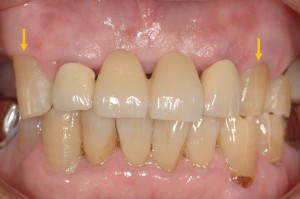

次の写真です。

虫歯を除去して、歯茎を一部切開し上顎から採取した歯肉を移植しました。移植した部分は真皮用創傷治癒材のテルダーミスを移植しています。

術前→9日後→3週間→5周後→1年2ヶ月後です。5週後で少し歯茎が退縮しますが、その後歯茎が成熟し厚みも増して「クリーピング」が起こって虫歯の部分を完全に歯茎で覆うことが出来ました。縦切開を入れていないので術後も綺麗です。